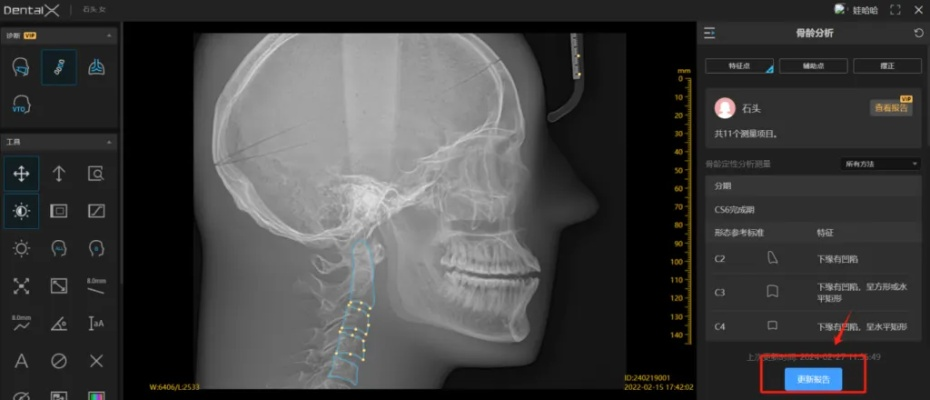

骨骼扫描官方下载和广电新版本,详细数据解释定义|DX版1_v9.914

一、什么是“骨骼扫描官方下载和广电新版本,详细数据解释定义_DX版1_v9.914”?答:“骨骼扫描官方下载和广电新版本,详细数据解释定义_DX版1_v9.914”是一款结合骨骼扫描技术与广电新版本的软件,用于对骨骼...

骨骼扫描官方下载和广电新版本,数据设计支持计划|冒险版_v3.652

初始经典版本时间回溯到我们的软件刚刚诞生的时代,那时的骨骼扫描官方下载和广电新版本数据设计支持计划冒险版还处于初始的经典版本,这个版本主要为用户提供了基础的骨骼扫描功能,以及广电行业的基础数据管理,这是我们的起点,为...